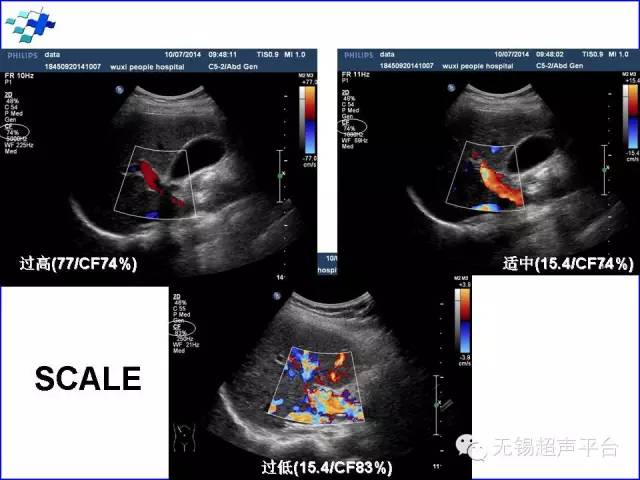

速度标尺(scale):有 kHz、cm/sec、m/sec选项。一般选择cm/sec。平衡(balance):控制叠加在二维超声图像上的彩色信号,可使彩色信号仅在血管壁内显示,不产生外溢。可选范围1~225。